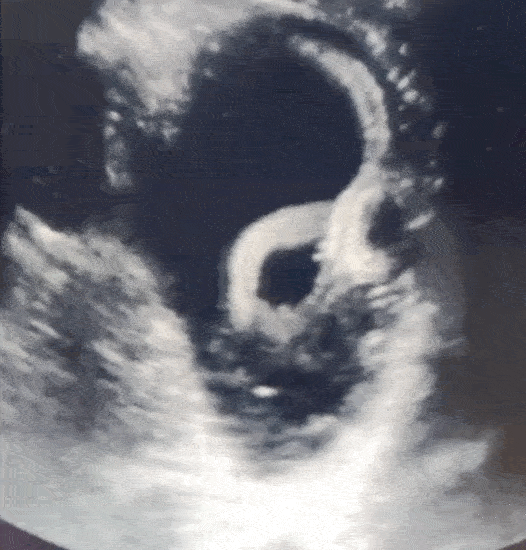

醫生對患者的下腔靜脈(靠近腹部的一條大靜脈)進行了超聲波掃描,以檢查其血管中的血液水平。但在這一過程中,他們意外窺見他的胃內有一個管狀結構並伴隨着捲曲運動(見下面的動圖)。